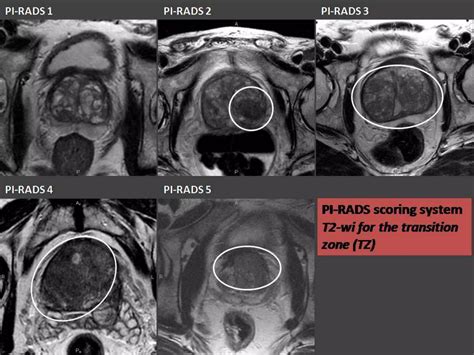

• Multiparametric MRI (mpMRI): This technique combines multiple MRI sequences, including T2-weighted imaging, diffusion-weighted imaging (DWI), and dynamic contrast-enhanced (DCE) imaging, to provide a comprehensive evaluation of the prostate.

• Prostate Imaging Reporting and Data System (PI-RADS): This standardized reporting system helps radiologists interpret MRI findings and classify the likelihood of clinically significant prostate cancer.